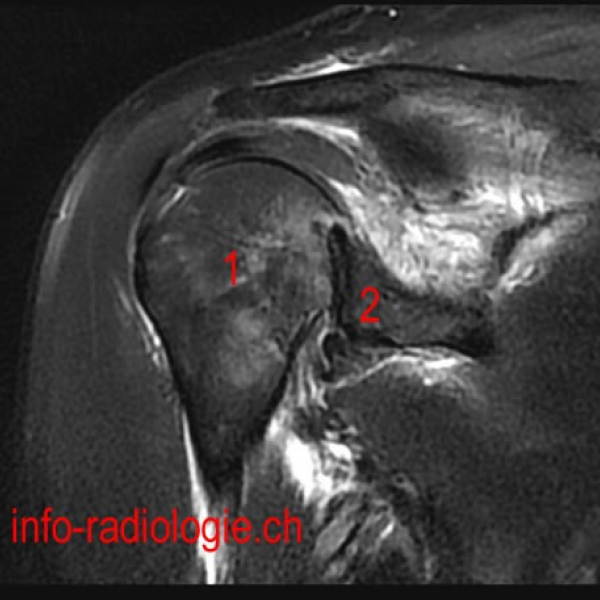

Resonancia nuclear magnetica de articulaciones de miembro superior (especifico) 883512 Idime. (2022)

Categoría:

Bogotá, Bucaramanga, Cali, Cucuta, Ibagué, Pereira

SKU/Código:

578

Precio:

$350000

IDIME. Instituto de Diagnóstico Médico. Código de Convenio : 8915